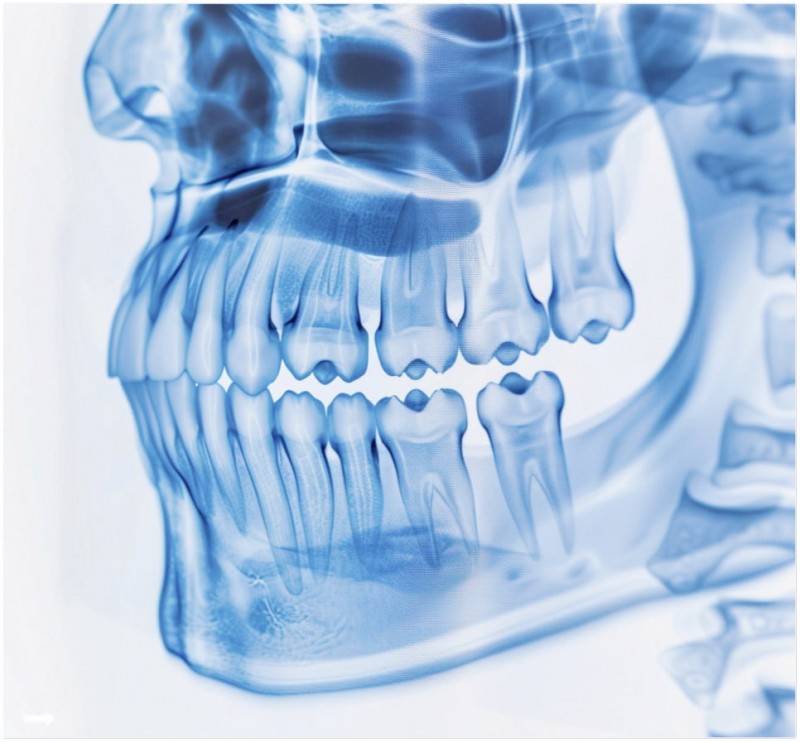

턱관절은 우리 몸에서 가장 복잡하면서도 자주 쓰이는 관절 중 하나예요.

하루에도 수천 번 움직이며 말하고, 씹고, 삼키는 동작을 도맡고 있죠.

우리 몸의 중심축이라 할 수 있는 상부 경추, 특히 목뼈 1번과 2번이 틀어지면

이게 두개골과 척추까지 영향을 줄 수 있거든요.

턱관절과 경추는 해부학적으로 아주 가까운 구조에 있기 때문이죠.

이런 관계로 인해 턱관절에 문제가 생기면, 목뼈 1번과 2번이 틀어지고